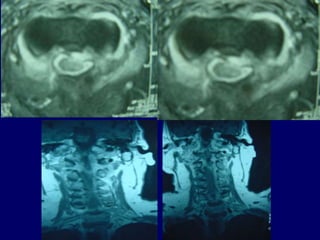

MRI